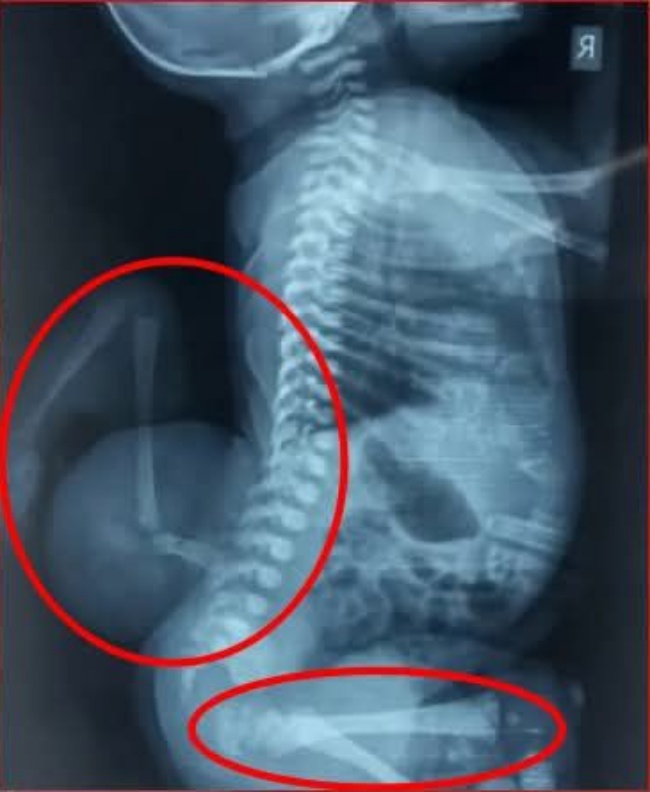

Born with a rare medical condition known as parasitic conjoined twinning, Aurelia entered the world facing challenges that most infants never experience. In this condition, one twin does not fully develop and remains attached to the other, leaving the surviving baby’s body to carry the additional physical burden. For such a small child, it is a situation that requires careful monitoring and specialized medical support.

Medical specialists note that cases involving parasitic twins are extremely uncommon and typically require careful evaluation by pediatric and surgical experts. With modern medical care, many children born with complex conditions have opportunities for treatment plans designed to improve comfort, health, and long-term development.